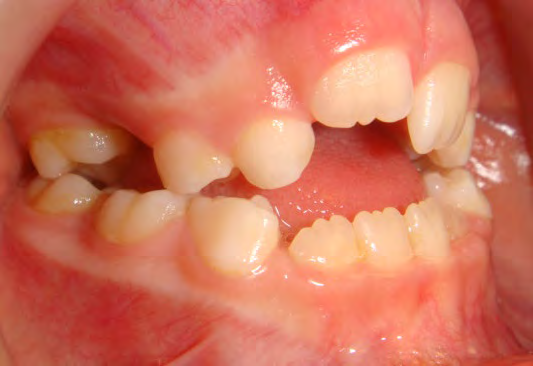

All of the patients below had been told they required extractions by orthodontists, some insisting that they could not be treated without extractions.

They were all treated without extractions, head gear or facemasks at Vakresmil and represent just a small sample of cases treated between 2004–2014.

The patient below had severe crowding of both upper canines and the lower right 5. The upper 4’s and 2’s were actually in contact.

Below are cases treated at Vakresmil without extractions within the last three years. The families had been told, “It is simply not possible for your child to be treated without extractions” by orthodontists. Judge for yourself if that was right or wrong.